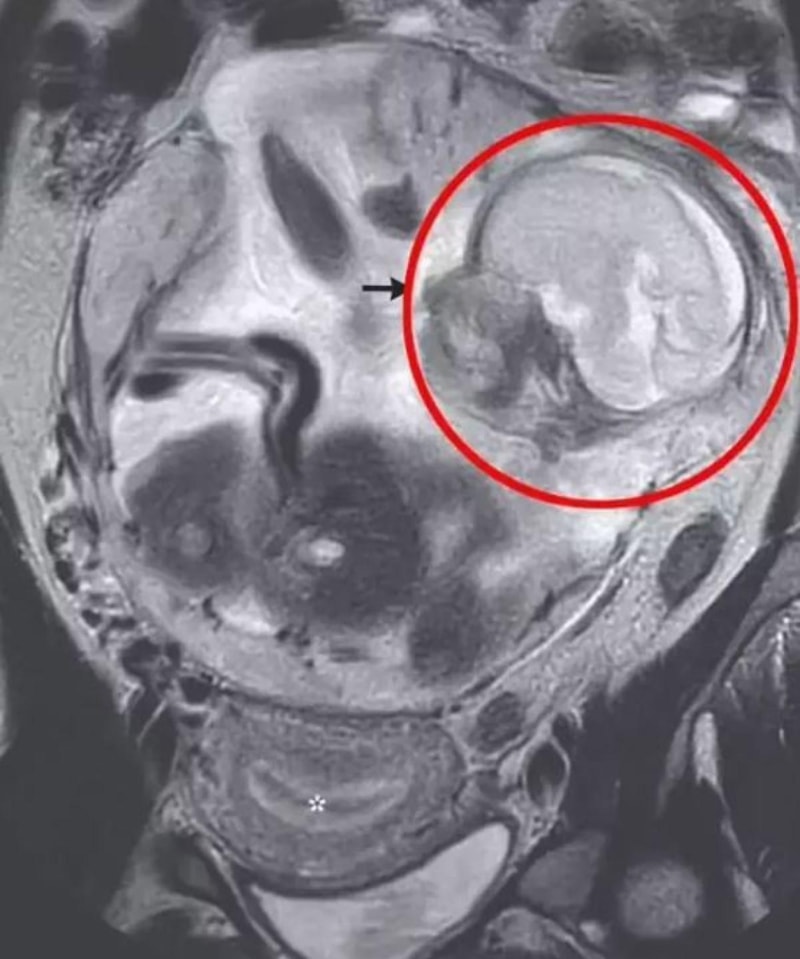

Yapılan testler ve muayeneler sonucunda hamile kadına ektopik gebelik (dış gebelik) teşhisi konuldu. Ektopik gebelikte fetüs annenin rahminde değil, karın boşluğunda bağırsaklarının yanında büyüdüğü tespit edildi.

Herkesi şaşkına çeviren çok nadir görülen bu vaka, "New England Journal of Medicine" dergisinde yayınlanmış olan bir makale ile kısa sürede gündem oldu.

Makalede aynı vaka üzerinde doktorlar, bebeğin 24 haftadan itibaren rahim dışında yaşayabileceğini, fakat hayatta kalma olasılığının yüzde 68 olduğunu belirtti.